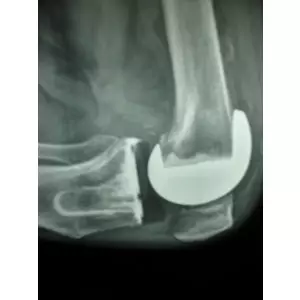

Ratibhai Patel

hip replacement surgery

Ratibhai Patel Details